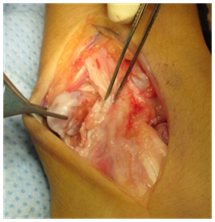

The surgery was done later on under general anaesthesia and with tourniquet control, the right wrist was approached dorsally with a longitudinal incision over the 4/5 extensor compartment, the capsule was opened with a ligament sparing technique, and a very large cartilaginous bone tumour, suggesting a osteochondroma, was found extended from dorsal to volar and to the ulnar side, sitting the main mass distal to the triangular fibrocartilaginous complex, where appeared to grow in a more round, smooth shape (Figure 3A-3D).

Figure 3A Ulnar side of the osteochondroma.

Figure 3B Removal of ulnar extension of the osteochondroma.

Figure 3D Seen clearly the distal portion of the TFCC undamaged.